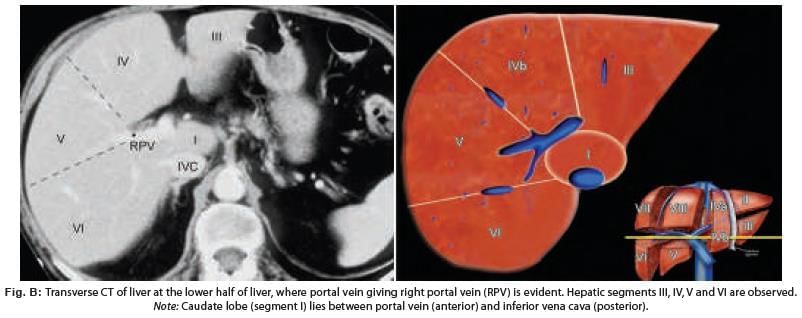

Liver is divided into eight segments according to Couinaud’s classification based upon. (AIIMS May 2019)

In CT scan of liver, identify the arrow marked segment: (INI-CET Nov 2022)